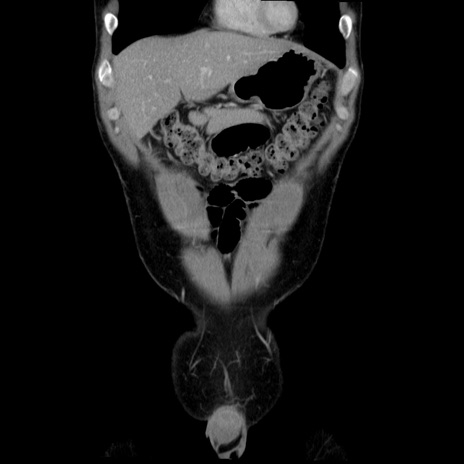

横断像

症例36(冠状断像)

【症例】20歳代 男性

【主訴】心窩部痛

【現病歴】今朝より上腹部痛あり。一旦軽快していたが再度出現したため救急要請。昨日夕に白身の魚を含む刺身を食べた。

【身体所見】BP 136/89mmHg、HR 74/min、BT 37.0℃、腹部:膨満、軟、心窩部に圧痛あり。反跳痛なし、筋性防御なし、腸雑音やや亢進あり。

【データ】WBC 17700、CRP 0.48